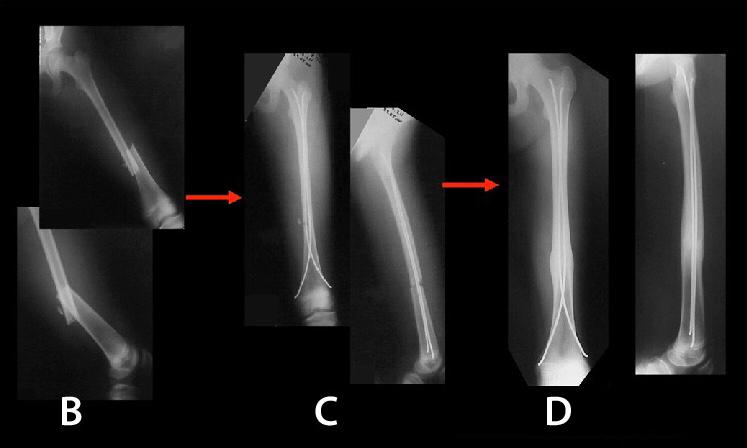

TITANIUM ELASTIC NAILING (TEN)

Titanium Elastic Nailing (TEN) is intended for fixation of diaphyseal fractures of long bones where the medullary canal is narrow or flexibility of the implant is paramount. The biomechanical principal of the Titanium elastic nailing is based on the symmetrical bracing action of two elastic nails inserted into the metaphysis, each of which bears against the inner bone at three points. The complication rates associated with Titanium elastic nailing have been reported to be minimal.